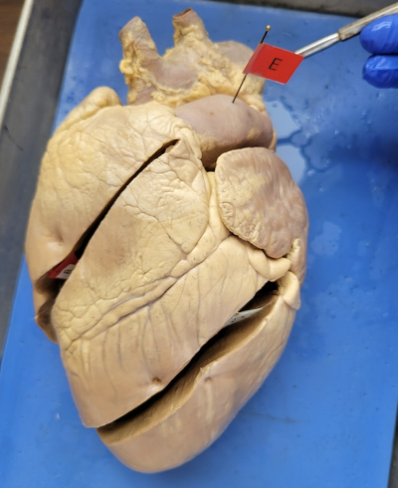

what is this

right ventricle